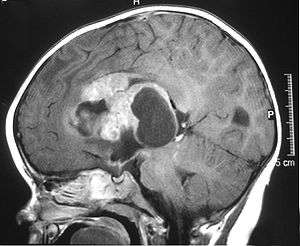

MRI of an AT/RT | |

Appearance on radiologic exam

AT/RTs can occur at any sites within the CNS; however, approximately 60% are located in the posterior fossa or cerebellar area. The ASCO study showed 52% posterior fossa; 39% sPNET (supratentorial primitive neuroectodermal tumors); 5% pineal; 2% spinal, and 2% multi-focal.[1]

The tumors' appearance on CT and MRI are nonspecific, tending towards large size, calcifications, necrosis (tissue death),and hemorrhage (bleeding). Radiological studies alone cannot identify AT/RT; a pathologist almost always has to evaluate a brain tissue sample.

The increased cellularity of the tumor may make the appearance on an uncontrasted CT to have increased attenuation. Solid parts of the tumor often enhance with contrast MRI finding on T1 and T2 weighted images are variable. Pre-contrast T2 weighted images may show an iso-signal or slightly hyper-signal. Solid components of the tumor may enhance with contrast but do not always. MRI studies appear to be more able to pick up metastatic foci in other intracranial locations as well as intraspinal locations.